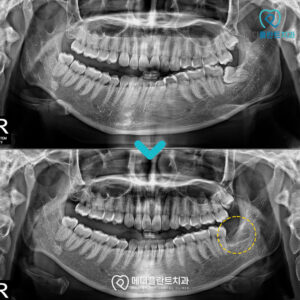

춘천수면치과 편안한 식사와 자연스러운 웃음을 위해! . 안녕하세요 🙂 춘천수면치과 메디플란트치과입니다. . 자연의 섭리에 따라 나이가 들면 누구나 노화 현상을 겪게 되는데요. . 신체 기능의 저하뿐 아니라 치아의 기능적인 부분…